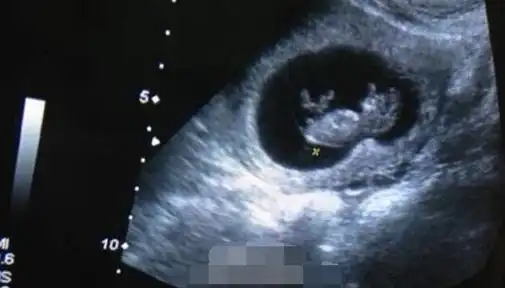

陈龙章龄之闪婚闪孕 双喜临门甜蜜晒婴儿b超照

欧弟晒妻子怀孕b超照:跟老天爷又申请一个账号